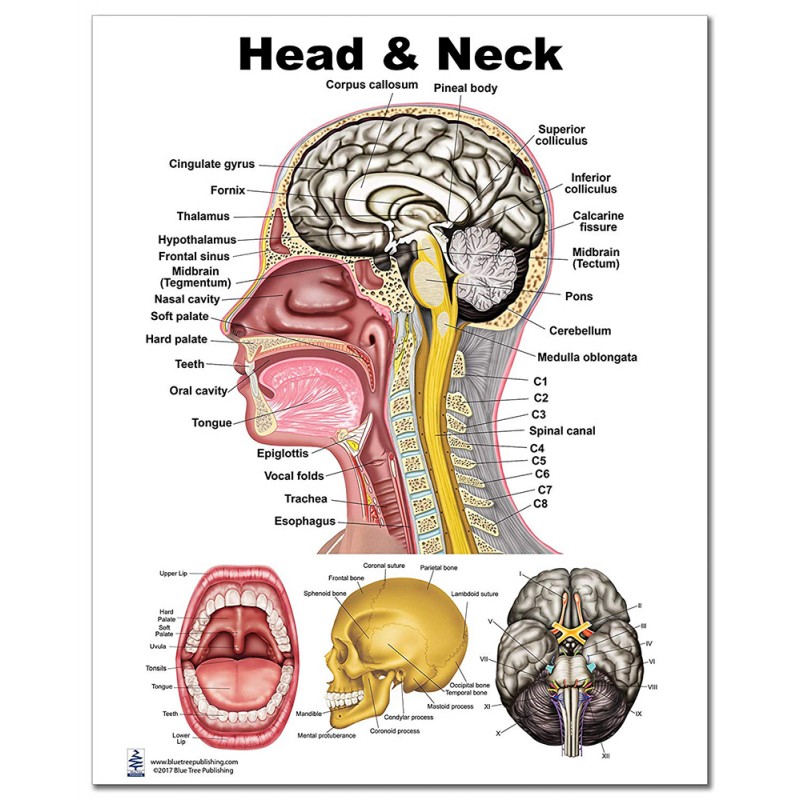

Head Neck anatomy: chapters 6-7 vascular system and glandular tissue. 80 terms. karatwiner. Preview. CDA 104 Instrument ID Ch. 34,35. 39 terms. - is an amalgamation of components of all of the systems of the body - head and neck region is connected to other regions - internally there is the brain - inferiorly there is the thorax - laterally.

Anatomy Head and Neck Practice Questions. What are the boundaries of the submental triangle and what does it contain? Click the card to flip 👆. a. Body of hyoid bone, anterior bellies of both Diagastrics, Mylohyoid forms floor. b. Contents: 2-4 lymph nodes, veins that unite to form anterior jugular vein. Click the card to flip 👆.

Test your knowledge of the anatomy of the head and neck with this quiz. Explore topics such as the hyoid bone, larynx, swallowing process, temporomandibular joint, muscles of mastication, muscles of the neck, orbit structure, layers of the globe, and eye movement. Sharpen your understanding of these critical anatomical structures and their functions.

Are you looking to test your knowledge of the head and neck region? Take our quiz to see how well you know the anatomy and structures of the face, sinuses, oral cavity, and pharynx. From the blood supply of the scalp to the muscles of the pharynx, this quiz covers a variety of topics with keywords specific to the field. Test your understanding of the structures of the head and neck with our.

Test your knowledge of anatomy with this quiz on the structures and functions of the head and neck. From the eyelids and muscles of the face to the nasal cavities and pharynx, this quiz covers a range of topics related to the head and neck region. Learn about the anatomy of the eyes, nose, mouth, and throat while practicing your ability to recall important terms and functions. Challenge.